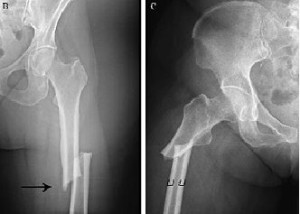

El riesgo de fractura atípica de fémur aumentó con la duración más prolongada del uso de bisfosfonatos y disminuyó rápidamente después de la interrupción del mismo. Los asiáticos tuvieron un riesgo mayor que los blancos. El riesgo absoluto de fractura atípica de fémur se mantuvo muy bajo en comparación con las reducciones en el riesgo de cadera y otras fracturas con el tratamiento con bisfosfonatos N Engl J Med, 20 de agosto de 2020

El uso prolongado de bifosfonatos reduce la resistencia a las fracturas

Luego de un uso promedio de 8 años, los bifosfonatos mostraban tejido cortical más mineralizado pero con menor resistencia al inicio y progresión de la fractura femoral. PNAS, 31 de julio de 2017